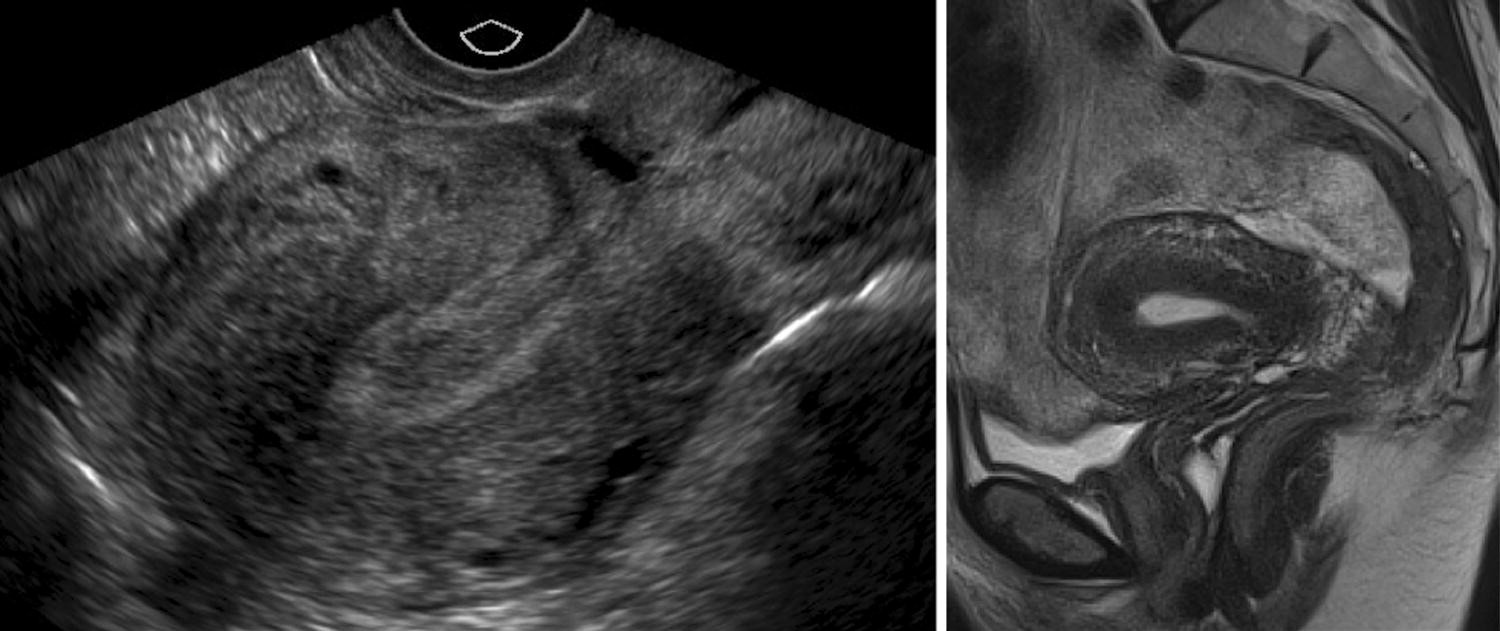

Heterogeneous uterus ultrasound radiology- MR imaging findings of MAP include dark intraplacental bands on T2weighted images, disorganized intraplacental vascularity, abnormal uterine bulge, heterogeneous placenta, thinning or loss of the retroplacental dark zone on T2weighted images, myometrial thinning or focal disruption of the myometrium, invasion of adjacent organs (particularly the bladder), and tentingMRI is the current imaging gold standard to diagnose adenomyosis, but access is often limited by high costs and availability Transvaginal ultrasound provides a costeffective, accurate and readily available alternative The objective of our study was to determine the diagnostic accuracy of commonly described sonographic findings in predicting uterine adenomyosis

Current treatments include hysterectomy, myomectomy, uterine artery embolization, magnetic resonance imaging (MRI)–guided focused ultrasound treatment, medical treatment based on hormone therapy (eg, progestin or gonadotropinreleasing hormone agonists), and endometrial ablation for women who are finished with childbearing The initial step in evaluating a woman with Sessile subserosal fibroids A little sessile subserosal fibroid on the superior face of the uterus (arrow) with heterogeneous low signal intensity on sagittal T2weighted image (TR 4,500 ms, TE 90 ms) (a) and with low signal enhancement on contrastenhanced fatsuppressed T1weighted image (TR 4 ms, TE 2 ms) (b)Another woman (c and d) with a sessile subserosal Transvaginal ultrasound shows an enlarged uterus with a finely heterogeneous echo pattern (Courtesy of Sherelle LaiferNarin, MD) FIGURE 1912 Two cases of

Haemorrhagic cellular leiomyoma Section Genital (female) imaging Case Type Clinical Cases Authors M Rosário Matos 1, Teresa Margarida Cunha 2 1 Department of Radiology, Hospital de Dona Estefânia – Centro Hospitalar de Lisboa Central 2 Department of Radiology, Instituto Português de Oncologia Francisco Gentil de Lisboa US shows a heterogeneous uterus with tubular anechoic spaces in the myometrium CDU shows a bright color mosaic of the vascular tangle CDU shows a bright color mosaic of the vascular tangle Spectral Doppler arterial waveforms are of highvelocity and lowresistance characteristic of arteriovenous shunting In some cases, the endometrium cannot be evaluated with ultrasound that may be due to fibroids, the position of the uterus or endometrial cancer These patients benefit from further evaluation with MRI ()Cases of endometrial cancer present with a thickened heterogeneous endometrium on T2 that enhances earlier than normal endometrium on dynamic gadolinium

Adenomatoid uterine tumors are rare, and their appearance on medical imaging modalities is not well established We present a case of an adenomatoid uterine tumor reviewing a unique sonographic presentation, magnetic resonance imaging (MRI), gross surgical appearance of the tumor, and microscopic pathology imagesUnlike ultrasound and magnetic resonance imaging (MRI), computed tomography (CT) is uterine arteries, branches of the anterior division of the internal iliac arteries (Fig 1) Yitta et al 13 described a fourth heterogeneous and multifocal enhancement pattern of the entire myometrium (Fig 4 and 10) Although ultrasound (US) is almost always the first modality used in the radiologic workup of endometrial disease, findings at sonohysterography, hysterosalpingography, magnetic resonance imaging, and computed tomography are often correlated with US findings